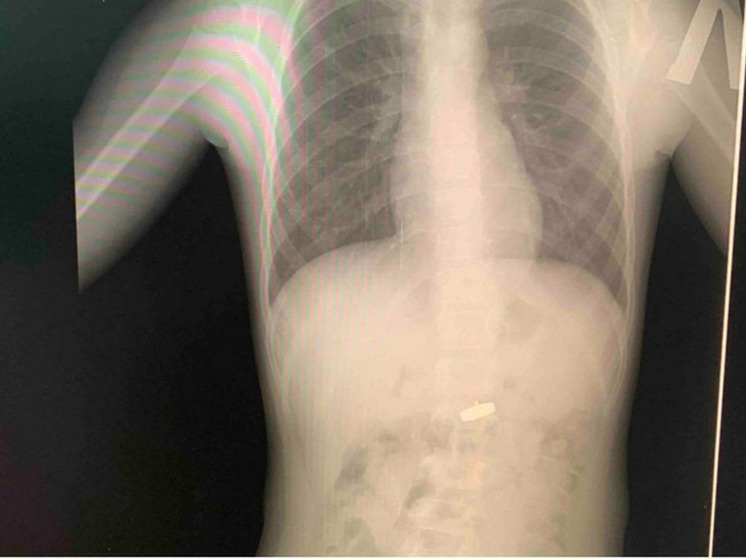

Фото: ЭГКБ №1

В Энгельсской городской клинической больнице №1 в Саратовской области врачам пришлось проводить экстренную операцию пятилетней девочке после того, как она проглотила магнит с прикрученным к нему острым шурупом. Родители обратились в медучреждение, когда у ребенка начались проблемы с пищеварением. После проведения рентгена врачи обнаружили в желудке маленькой пациентки инородное тело.

"Чтобы извлечь опасный предмет, девочке под общим наркозом была проведена эзофагогастродуоденоскопия – эндоскопическое исследование пищевода, желудка и двенадцатиперстной кишки", - сообщается в телеграм-канале клиники.